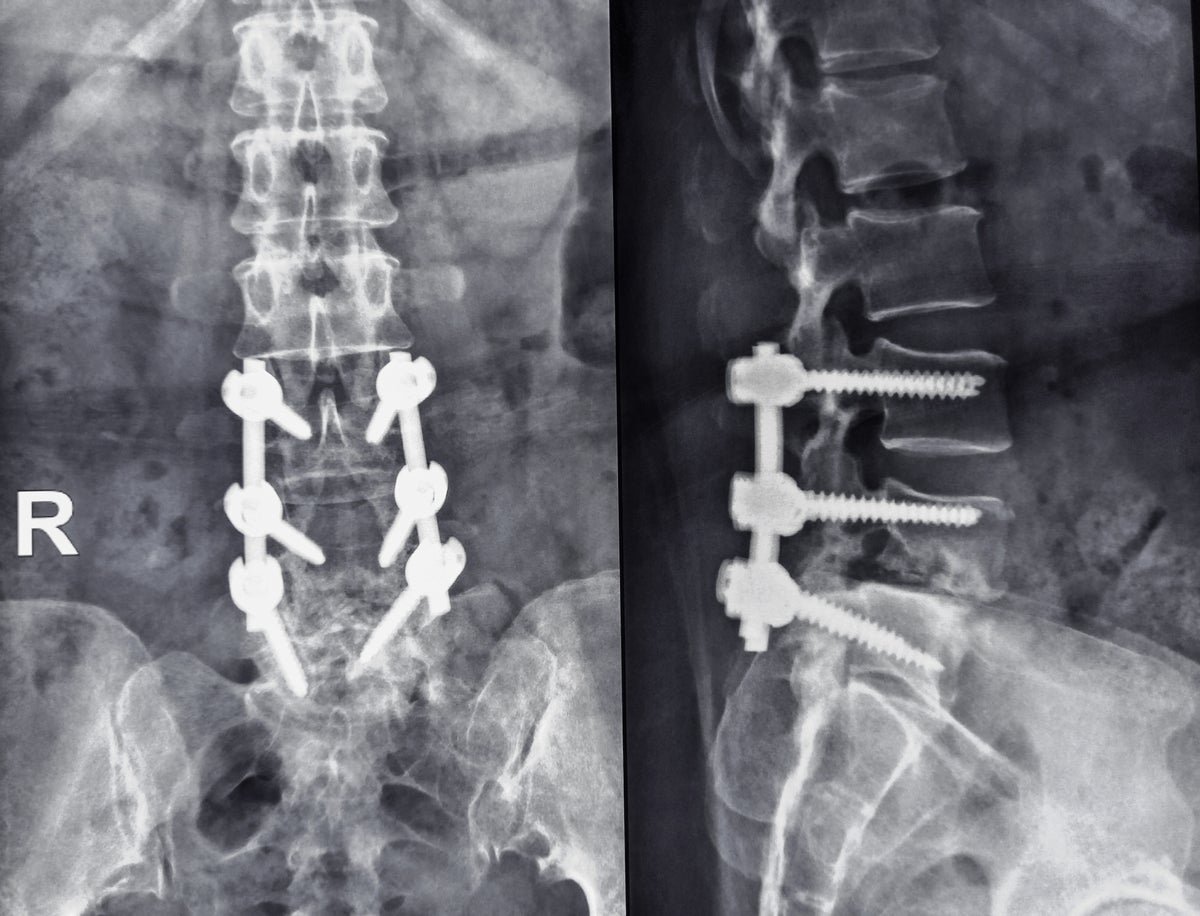

Plate and screw fixation radiograph of a human spine with lumbar spondylolisthesis beyond L4 and L5. Luigi Mangion posted a similar image on X, showing a four-bolt spine.

Luigi Mangione, the suspect charged with murder During the firing of UnitedHealthcare (UHC) CEO Brian Thompson, he suffered severe back pain allegedly caused by a condition called spondylolisthesis. Mangion told his friends The pain interfered with his ability to perform physical activities and his relationship life, according to The New York Times. He also told people that he needed surgery, and a photo at his expense in Xn (formerly Twitter) showed an apparent x-ray of a spine pierced by long rods and screws, a sign of surgery sometimes used to stabilize vertebrae if pain is not controlled by medication and physical therapy.

It was supposed to be Mangione not taking medication for back pain But she posted on spondylolisthesis-related Reddit threads and talked on Goodreads about reading books about back pain, According to CNN. He told a friend in Honolulu, where he had lived the year before the shooting, that he needed back surgery. In the summer of 2023, his friend texted him to ask how the surgery went, and Mangion sent him X-rays of his spine. The friend told CNN that the footage “looked horrible” and that she lost contact with Mangione after that.